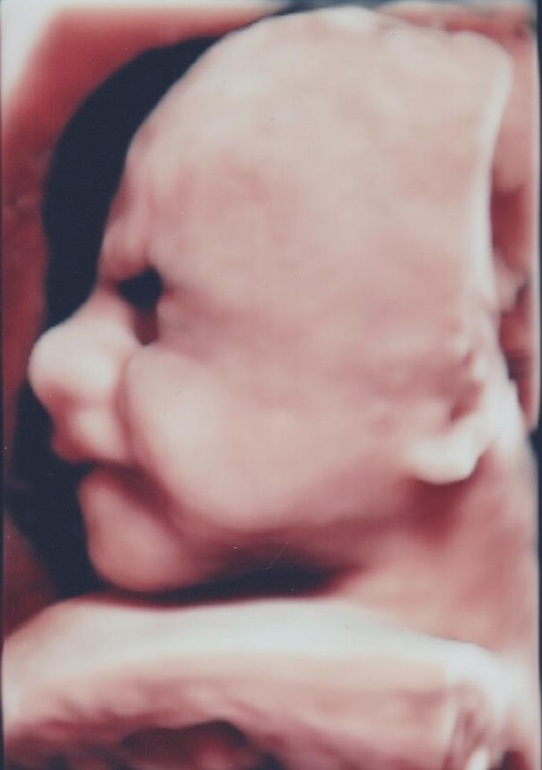

30-я. Узи и фотопуз

Фото пузиковНу что, третий триместр, с завтрашнего-сегодняшнего 30-я. Сходили на узи, иаж 27, по-прежнему лепят многоводие..... плацента 1-2 степени.... На следующей неделе потопаем на приём. Грохотуня уже 1250, пошёл с опережением не в 3 дня, а в неделю, так что ставят начало 30й. Если б знала, что будет путаница в сроке по АК и моя ранняя овуля, сразу бы сказала дату пм не 17.11, а 11.11.

узи, улыбался как мог)